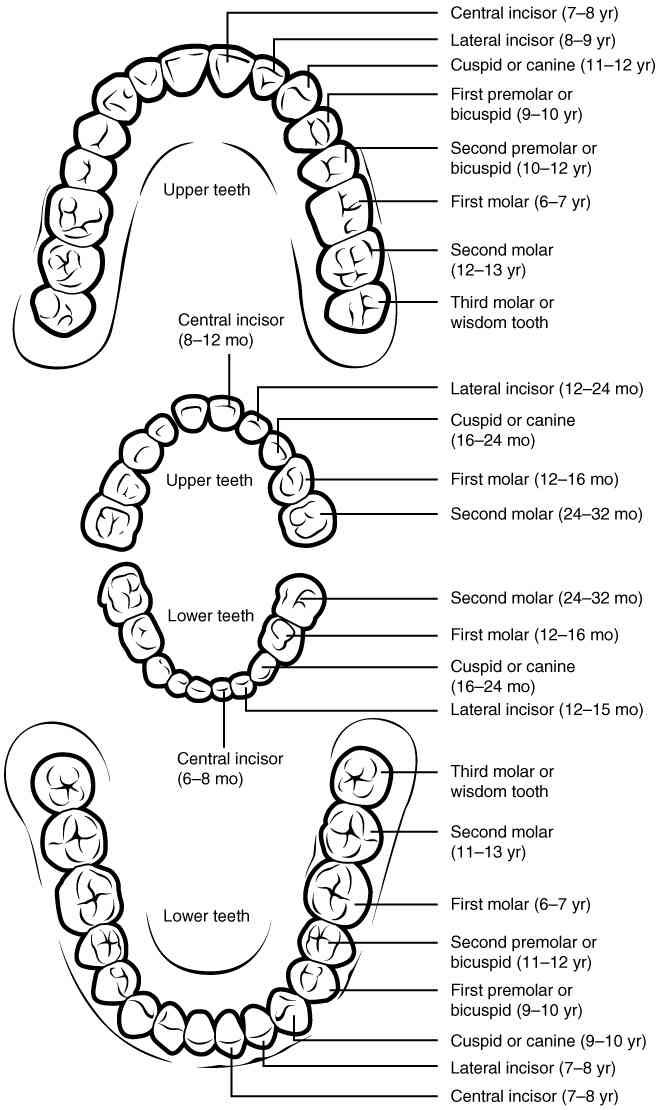

This page is under construction. For now, it is just a resource of the images found in the OpenStax Anatomy and Physiology Handbook. It wil slowly change into a revision tool. Each slide has a number. Use this to refer to the slide. When completed, it will have an unlabelled section, with labelled slides in parallel. On the unlabelled slides, write your answer and use the labelled slide to assess yourself. Keep track by also noting the number on each slide. Improvement at each attempt is important, more so than full marks on a first attempt.